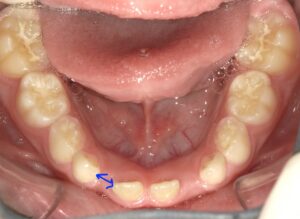

この場合、上は真ん中の歯に向かって尖った歯列になっています。下は矢印部分の

スペースが足りません。

そこでプレオルソを装着します。